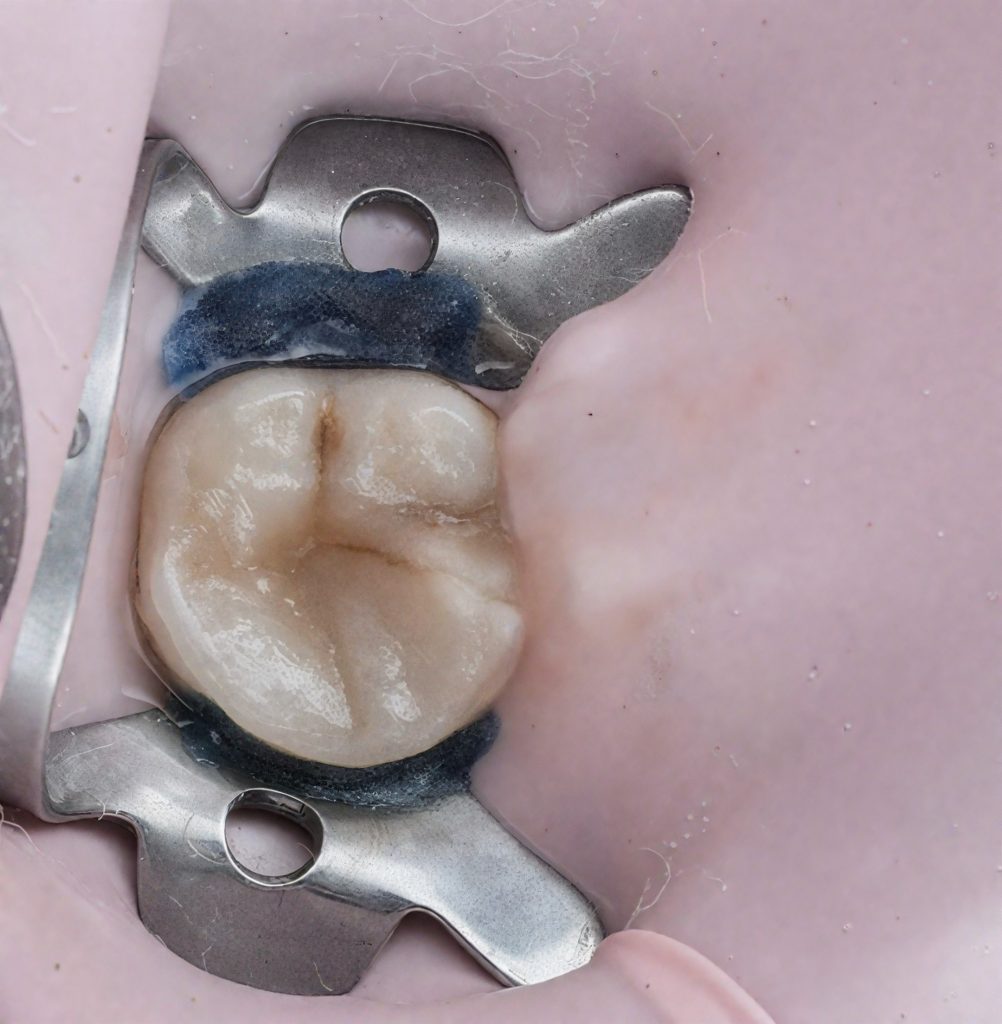

Full rubber-dam isolation was achieved using a pink dam for enhanced visibility (Fig 3). Conservative access under the dental microscope preserved pericervical dentin.

3️⃣ Rubber-dam isolation (pink dam)